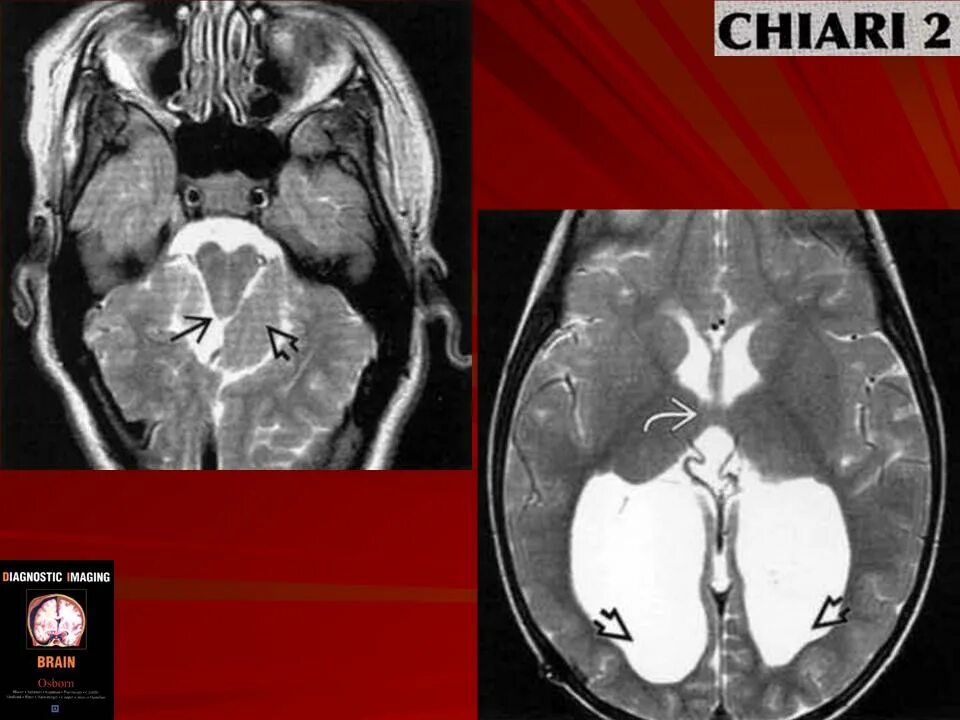

Код мкб арнольда киари